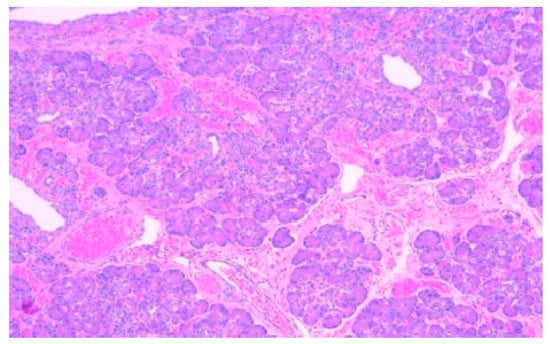

According to the Heinrich classification, modified by Gaspar-Fuentes et al., there are four histological types of EPT: type I—presenting acini, ducts, and islets (complete heterotopia), type II—presenting only ducts (canalicular heterotopia), type III—presenting only acini (exocrine heterotopia), and type IV—presenting only islets (endocrine heterotopia) [19]. 5 out of the 6 cases evaluated belonged to type I and 1 case belonged to type III (Figure 1, Figure 2, Figure 3 and Figure 4).

Figure 2. Ectopic pancreatic tissue within the submucosa of a Meckel diverticulum. In the left upper half of the image, the lining of the diverticulum is formed by oxyntic glands and gastric foveolar epithelium, HE, 100×.